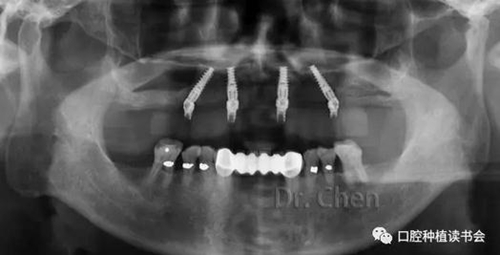

患者佩戴義齒后的口內(nèi)像和口外像(圖11、12),義齒外形、顏色、發(fā)音滿意,

曲斷片顯示所有氧化鋯接口與Multi-unit基臺(tái)之間完全就位,骨水平穩(wěn)定于植體頸部(圖13)。

患者佩戴永久修復(fù)體后半年復(fù)診,咀嚼功能及美觀、發(fā)音均滿意。骨水平穩(wěn)定,無(wú)機(jī)械及生物學(xué)并發(fā)癥。

13.jpg

▲ 永久修復(fù)后的曲斷片